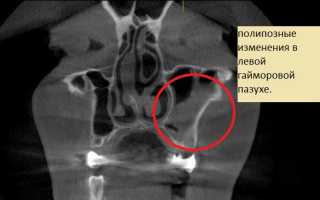

• КТ (дает возможность получить более точные данные о состоянии стенок верхнечелюстного синуса, а также других придаточных пазух носа и всех частях лицевого скелета);